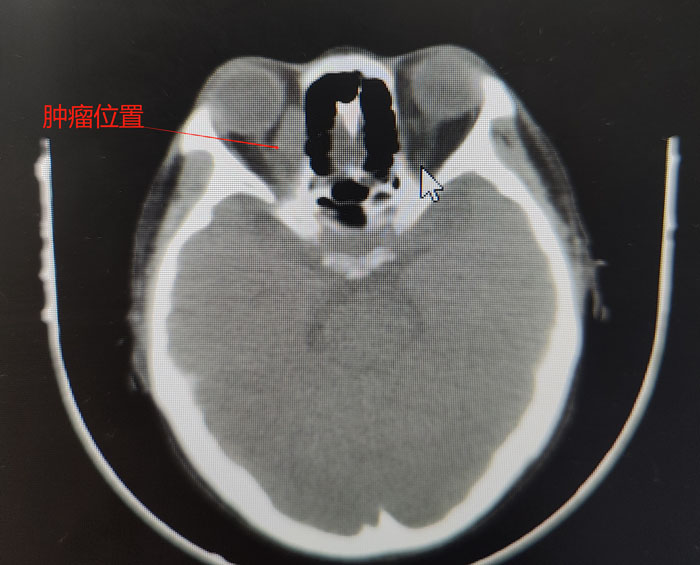

患者因乏力伴发热1周到当地医院就诊,检查显示全血细胞均明显减少,考虑血液系统疾病,当地医生建议到上级医院进一步诊治。随后,患者就诊于北京和省内多家医院,进行了骨髓穿刺、外周肿大淋巴结穿刺活检、PET-CT、全身核磁、基因检测等检查,仍不能明确病因。根据该患者的特殊情况,唯有眼眶肿物没有穿刺,因眼眶肿物距离眼球及眶周血管较近,且患者全血细胞非常低,很多医院眼科因风险较大未进行该操作。

患者的病情非常特殊,其眼眶肿物内下方距离眶缘1cm处有一根较大的动脉血管,而肿瘤内侧又紧挨着眼球,一旦穿刺出血,在患者血小板及白细胞危急值的状态下开眶止血,无疑是难上加难。其次,术后暴发感染的风险也难以控制。同时,穿刺是为了更好地明确病理,需要选用粗针,这又极大增加了穿刺风险……面对如此复杂的形势,在眼科肿瘤团队和纪晓惠主任医师的配合下,确定穿刺位置和进针方向、深度,经过三次“惊心动魄”的穿刺,顺利取出三条鱼肉状肿物组织,病理诊断后,疾病的“真容”终于露出水面,患者确诊为非霍奇金弥漫大B淋巴瘤。噬血细胞综合征考虑为淋巴瘤继发,需要积极控制淋巴瘤原发病。之后,患者前往果冻传媒